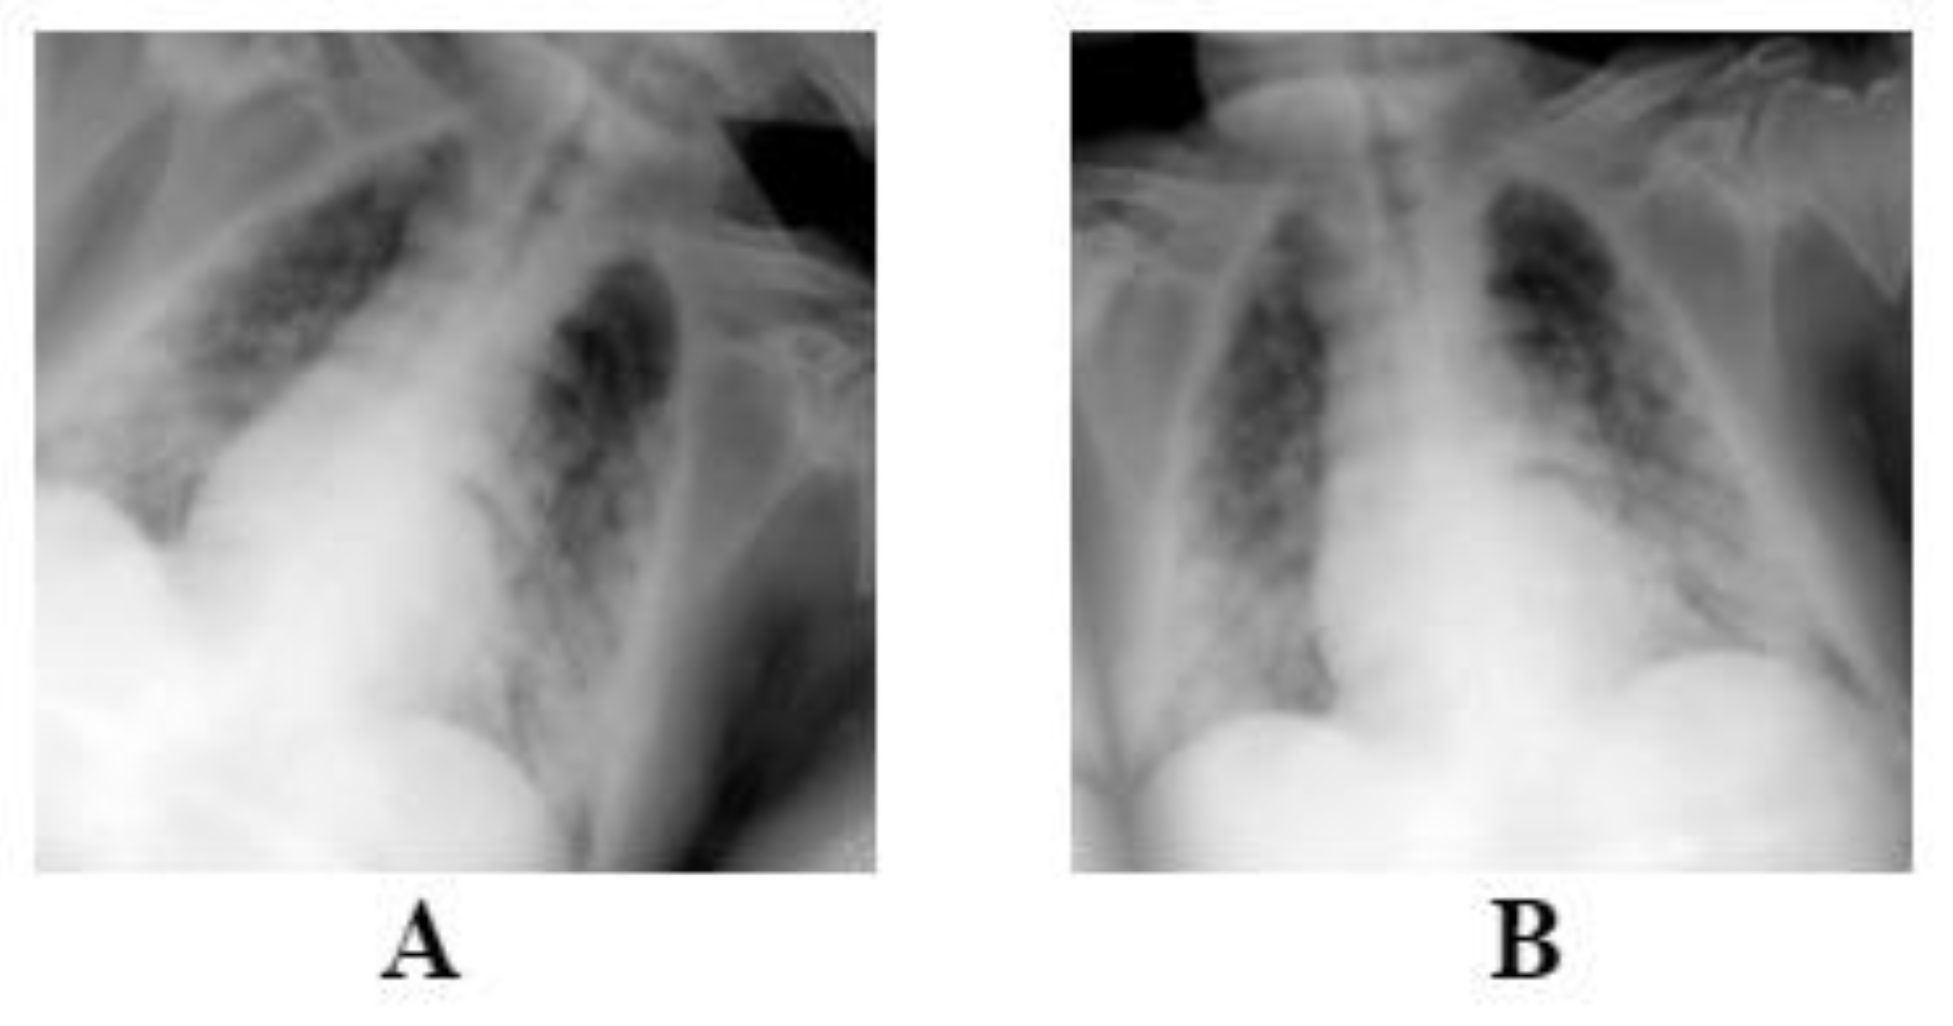

We utilized data augmentation methods, such as random rotation (±10°) and random horizontal flip (Figure 2), to deal with overfitting issues. The augmentations were applied randomly on each image, meaning that some images will only be rotated, flipped horizontally or both, as it is shown on Figure 2. These methods were applied on each image during model training on the training set and not before, leaving the original dataset intact without changes. Each architecture requires a specific image size; therefore, all images were resized to 224 × 224 for the ResNet and DenseNet models using bilinear interpolation. On the other hand, InceptionV3 can work with various sizes, therefore no resizing was needed.

Figure 2. The figure above is an example of the augmentations that is performed on each image. Image (A) is flipped and rotated, and image (B) is only rotated slightly.